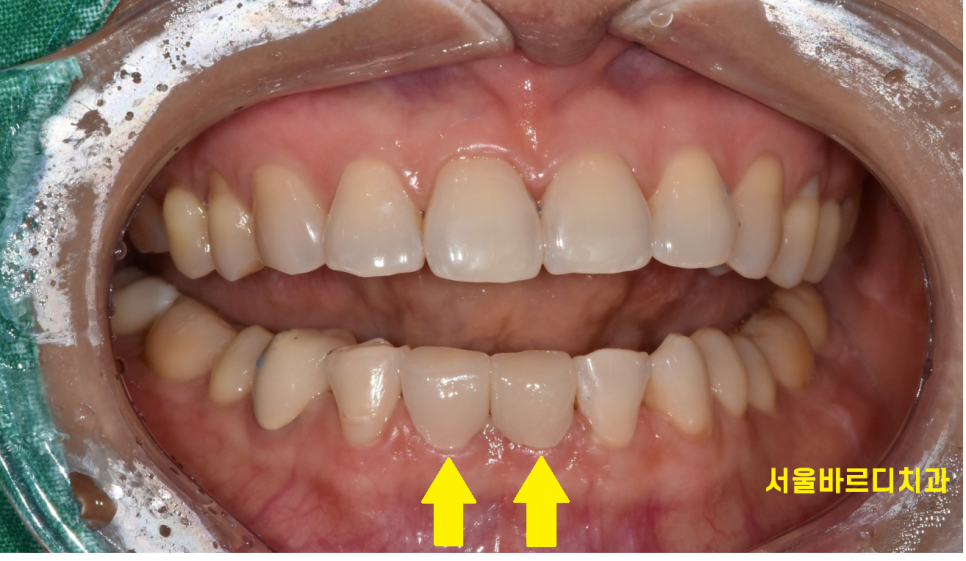

고덕동 치과 아래 앞니가 벌어져서 내원하셨는데요.

보니까 치아 주변으로 치석이 쌓여있네요~

1차적으로 치석부터 제거하고 재평가를 해보았습니다.

벌어진 아래 앞니 2개만 라미네이트를 우선 진행

주황색으로 표시한 부분을 사이가 보이지 않게

최대한 메꿔드리기로 하였습니다.